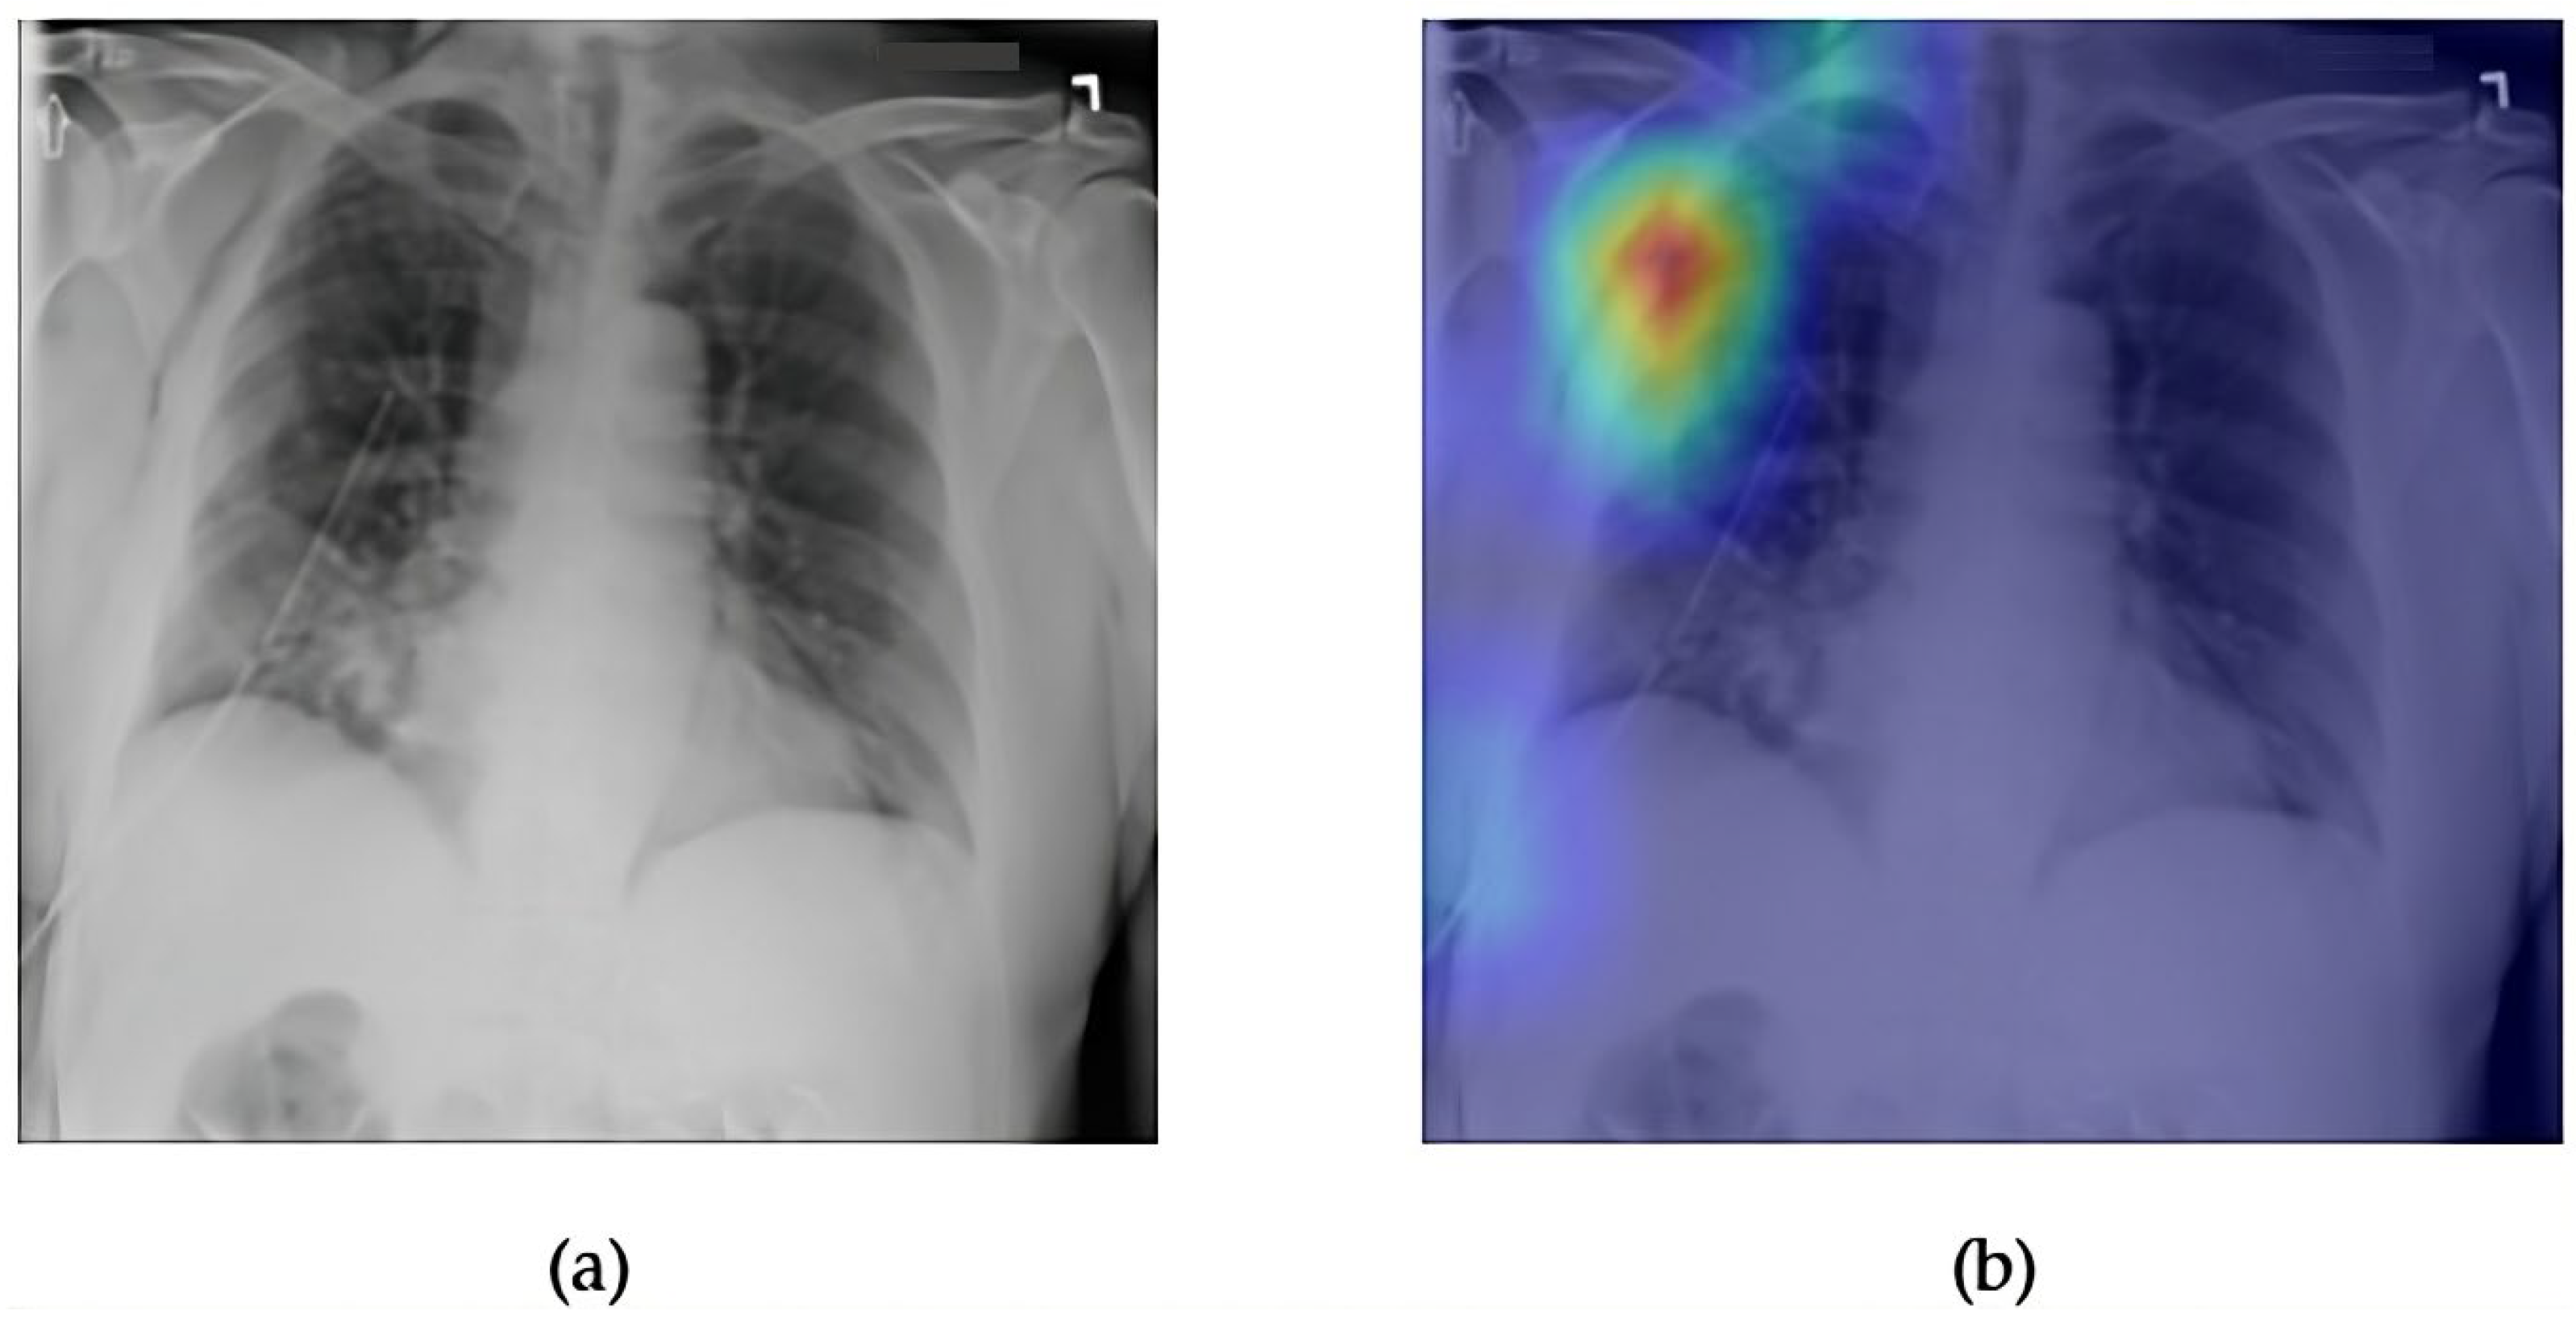

- Although our Grad-CAM-based explainability provides useful localization cues, it is inherently limited by its post hoc nature and reliance on gradient flow from the final convolutional layers. Future research could incorporate advanced interpretability techniques such as Layer-wise Relevance Propagation (LRP), Integrated Gradients, or attention rollouts in Transformers, which may offer a more complete understanding of model reasoning.